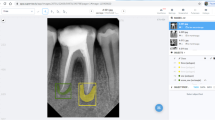

Orthodontically induced external root resorption (OIERR) is a common complication of orthodontic treatments. Accurate OIERR grading is crucial for clinical intervention. This study aimed to evaluate six deep convolutional neural networks (CNNs) for performing OIERR grading on tooth slices to construct an automatic grading system for OIERR. A total of 2146 tooth slices of different OIERR grades were collected and preprocessed. Six pre-trained CNNs (EfficientNet-B1, EfficientNet-B2, EfficientNet-B3, EfficientNet-B4, EfficientNet-B5, and MobileNet-V3) were trained and validated on the pre-processed images based on four different cross-validation methods. The performances of the CNNs on a test set were evaluated and compared with those of orthodontists. The gradient-weighted class activation mapping (Grad-CAM) technique was used to explore the area of maximum impact on the model decisions in the tooth slices. The six CNN models performed remarkably well in OIERR grading, with a mean accuracy of 0.92, surpassing that of the orthodontists (mean accuracy of 0.82). EfficientNet-B4 trained with fivefold cross-validation emerged as the final OIERR grading system, with a high accuracy of 0.94. Grad-CAM revealed that the apical region had the greatest effect on the OIERR grading system. The six CNNs demonstrated excellent OIERR grading and outperformed orthodontists. The proposed OIERR grading system holds potential as a reliable diagnostic support for orthodontists in clinical practice.

Selvaraju RR, Cogswell M, Das A, Vedantam R, Parikh D, Batra D: Grad-CAM: Visual Explanations from Deep Networks via Gradient-Based Localization. In: 2017 IEEE International Conference on Computer Vision (ICCV), 2017, pp 618–626.